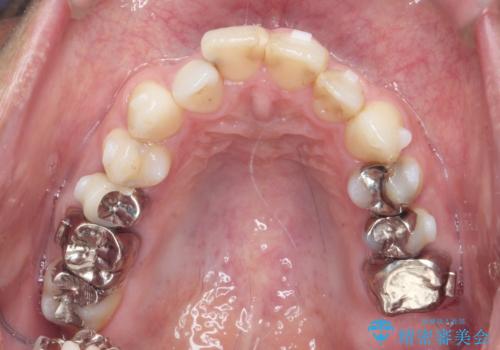

矯正と虫歯のセラミック治療 総合歯科治療の実践

- 突き出た前歯の角度の改善と虫歯治療の改善を求めて来院されました。

虫歯を除去したのち、マウスピース矯正治療を行い、歯並びやがたつきを改善したのち、セラミックに置き換えることで審美性の向上を計画します。